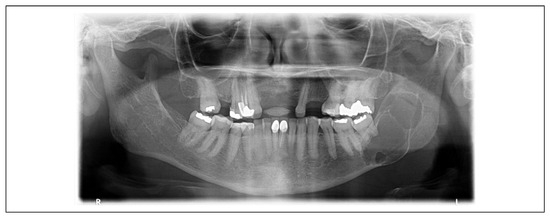

| 1 | 3.1 × 3.7 = 11.47 cm2 | 1.9 × 1.9 = 3.61 cm2 | 68.52% | Moderate reaction |

| 2 | 7.5 × 3.5 = 26.25 cm2 | 5.5 × 1.6 = 8.80 cm2 | 66.47% | Moderate reaction |

| 3 | 3.5 × 3.6 = 12.60 cm2 | 2.1 × 1.9 = 3.99 cm2 | 68.33% | Moderate reaction |

| 4 | 2.0 × 2.2 = 4.40 cm2 | 0.8 × 0.7 = 0.56 cm2 | 87.27% | Good reaction |

| 5 | 3.8 × 9.1 = 34.58 cm2 | 2.7 × 5.7 = 15.39 cm2 | 55.49% | Moderate reaction |

| 6 | 4.2 × 4.7 = 19.74 cm2 | 0.7 × 0.7 = 0.49 cm2 | 97.51% | Good reaction |

| Total | 18.17 cm2 | 5.47 cm2 | 73.93% | Moderate reaction |